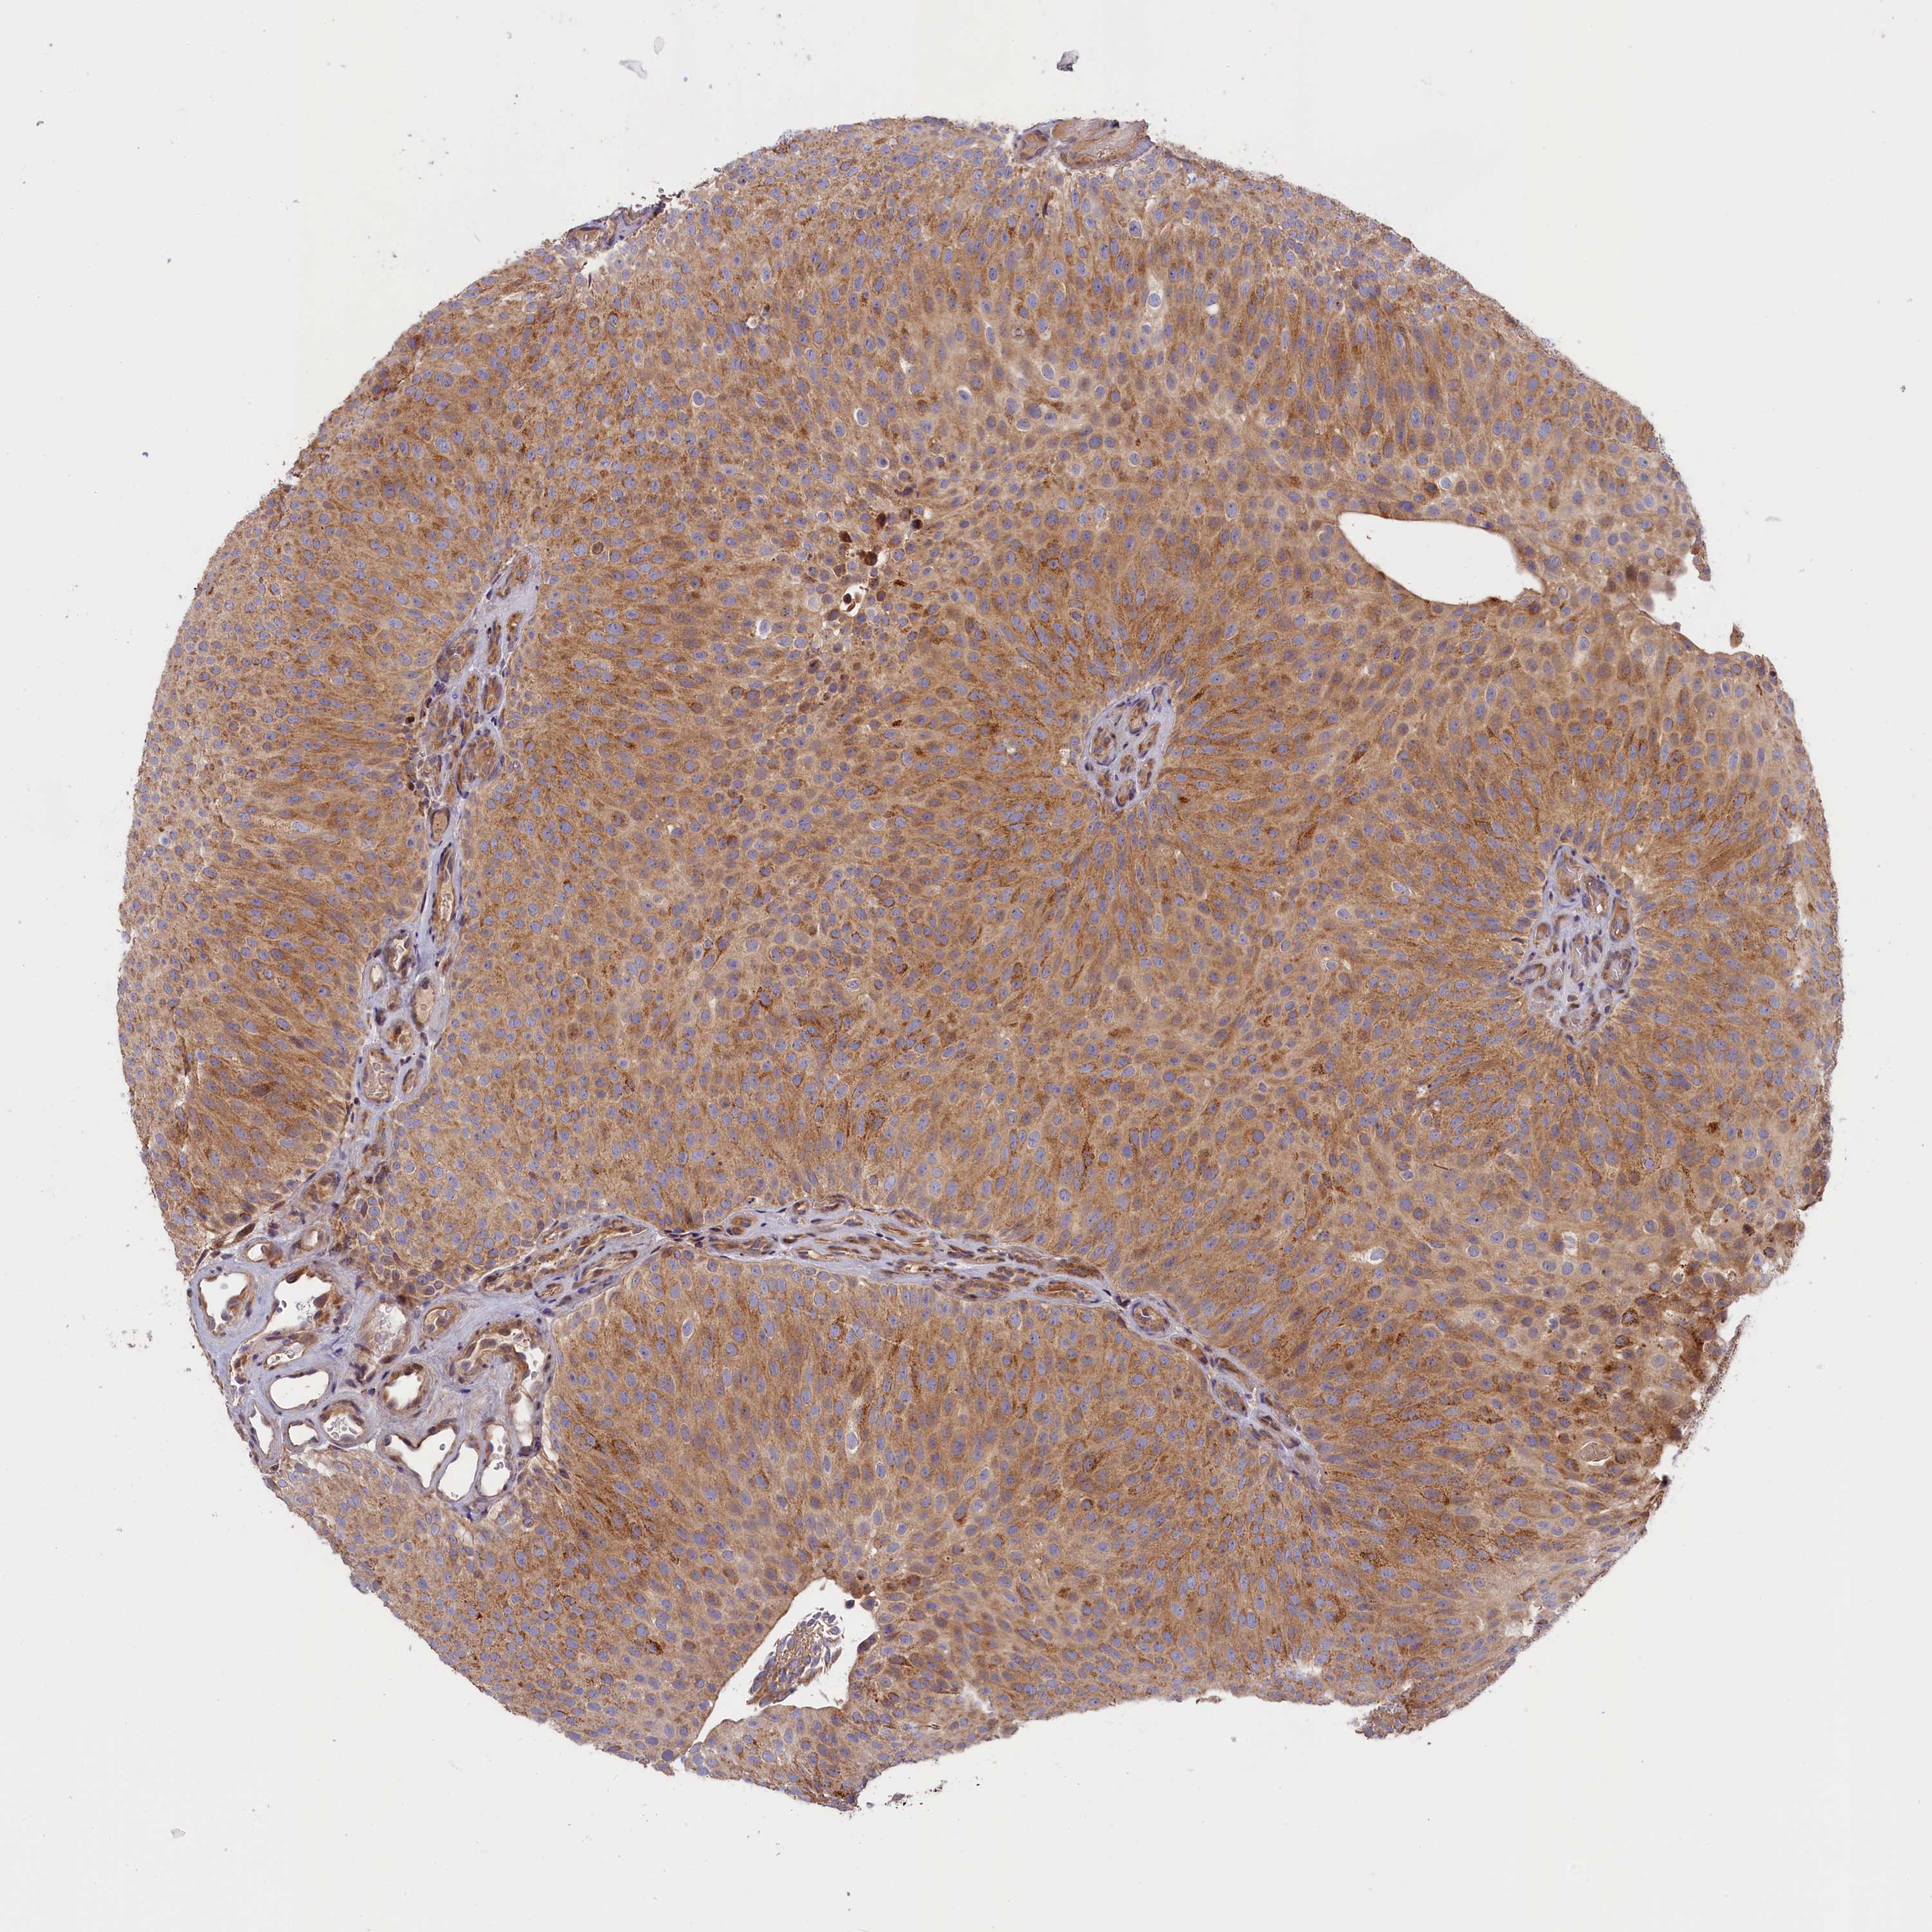

UROTHELIAL CANCER - Protein expressioni

A mouse-over function shows sample information and annotation data. Click on an image to view it in a full screen mode. Samples can be filtered based on level of antibody staining by selecting one or several of the following categories: high, medium, low and not detected. The assay and annotation is described here.

Note that samples used for immunohistochemistry by the Human Protein Atlas do not correspond to samples in the TCGA dataset.

Antibody stainingi

Antibody staining in the annotated cell types in the current human tissue is reported as not detected, low, medium, or high, based on conventional immunohistochemistry profiling in selected tissues. This score is based on the combination of the staining intensity and fraction of stained cells.

Each image is clickable and will lead to virtual microscopy that enables deeper exploration of all samples and also displays staining intensity scores, fraction scores and subcellular localization as well as patient and tissue information for each sample.

Antibody HPA041515

Antibody HPA041835

Urothelial carcinoma, High grade

Urothelial carcinoma, Low grade